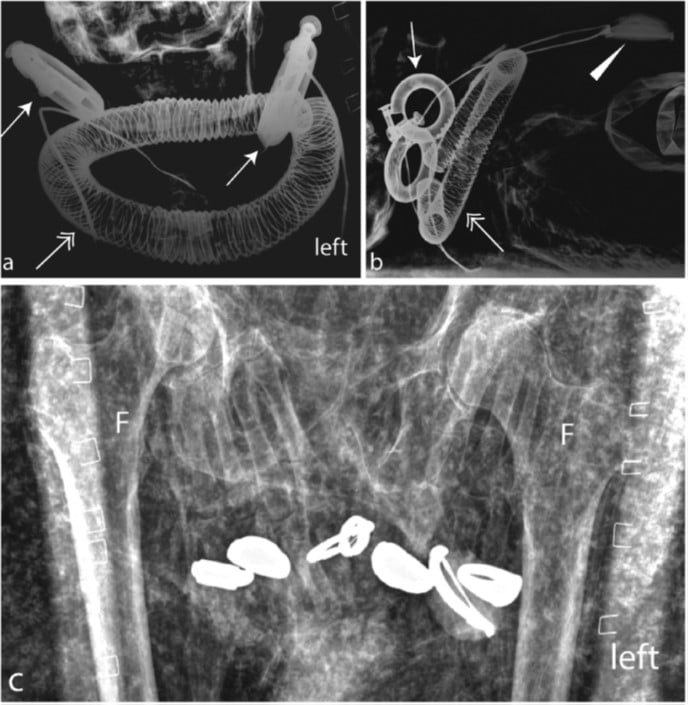

La descrizione della tomba fu talmente poco entusiasmante che Maspero concesse a Schiaparelli di tenere tutti i reperti ritrovati. Riportati quasi in sordina a Torino, sono rimasti pressoché lasciati a loro stessi per decenni, fino al 2016, quando un fondo di ricerca svizzero (!) dedicato al rituale dei vasi canopici ma anche al riconoscimento delle mummie egizie ha permesso di analizzare anche dei resti umani che erano stati ritrovati nella tomba. Per essere precisi: un ginocchio pressoché completo (parte distale del femore, patella e parte prossimale della tibia), la parte distale di un secondo femore e quella prossimale di una seconda tibia.

L’analisi radiografica delle due gambe che ha permesso di determinarne età, corporatura ed altezza presunta. A destra: evidenziate le calcificazioni delle arterie tibiali ad ulteriore conferma dell’età presunta al momento del decesso